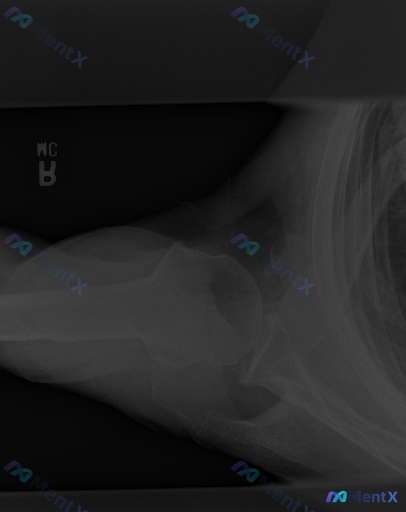

网上看到一份右肩关节腋位的X线影像资料和结构化分析,有点意思—— 影像报告的结论很明确: - 肱骨近端、肩胛带骨骼结构完整,皮质连续,无骨折透亮线 - 腋位下肱骨头与肩胛盂对合良好,无脱位/半脱位 - 关节间隙正常,无明显骨赘、钙化或软组织肿胀 总体印象:未见明显影像学异常 但问题是,假设这个病例是...